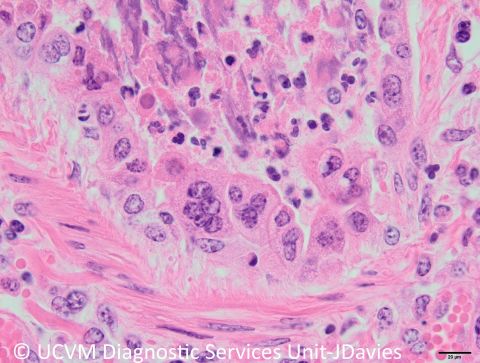

Species: Ruminant, Bovine (calf)

Undifferentiated neonatal diarrhea caused by bovine coronavirus